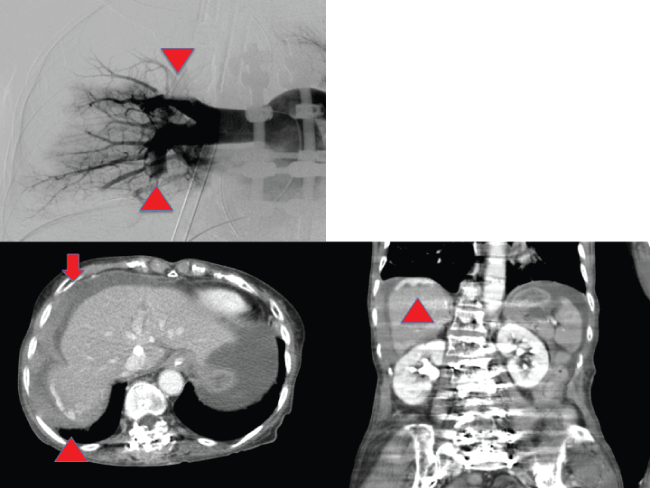

Unexpectedly, she fell into PEA and CPR was started. Chest compressions contributed to the start of VA-ECMO under radiography. Arterial angiography revealed thromboembolism of the right upper and lower pulmonary artery branches. The patient received an immediate infusion of 5,000 units of unfractionated heparin. We diagnosed her with pulmonary thromboembolism due to deep vein thrombosis resulting from spinal surgery (Figure 1). Although her vital signs stabilized, VA-ECMO could not work smoothly due to hypovolemic state. Ultrasonography revealed an echo-free space in the abdominal cavity. CE-CT revealed an intra-abdominal fluid collection and liver injury at the posterior area (Figure 1). No bone fractures near the liver were found. Transfusion could not improve the patient's unstable state, and angiography could not detect the injured vessels; therefore, we performed laparotomy for hemostasis. Massive bloody ascites were found and the infra-diaphragmatic area of liver was found to be damaged (Figure 2). We decided to perform DCS to control massive hemorrhage. Peri-hepatic gauze packing and transient abdominal closure were performed. In the ICU, the patient was treated with a massive transfusion. Despite transfusion and warming, hemorrhage was not controllable, and therefore the patient was re-admitted to the operating room for confirmative peri-hepatic gauze packing. With stabilization of her vital signs, abdominal wall closure was performed after a 40 hour interval from laparotomy. After tracheotomy at 22 hospitalized days, continuous rehabilitation could contribute to improvement of her of activities of daily living.

Figure 1: (Left upper) Arrowheads show obstruction of the upper and lower branches of the pulmonary artery in right pulmonary angiography; (Left lower) Arrow demonstrates fluid collection in the abdominal cavity in CE-CT. Arrowhead shows extravasation at the posterior segment in CE-CT at axial figure; (Right lower) Arrowhead shows extravasation at the posterior segment in CE-CT at coronal figure.